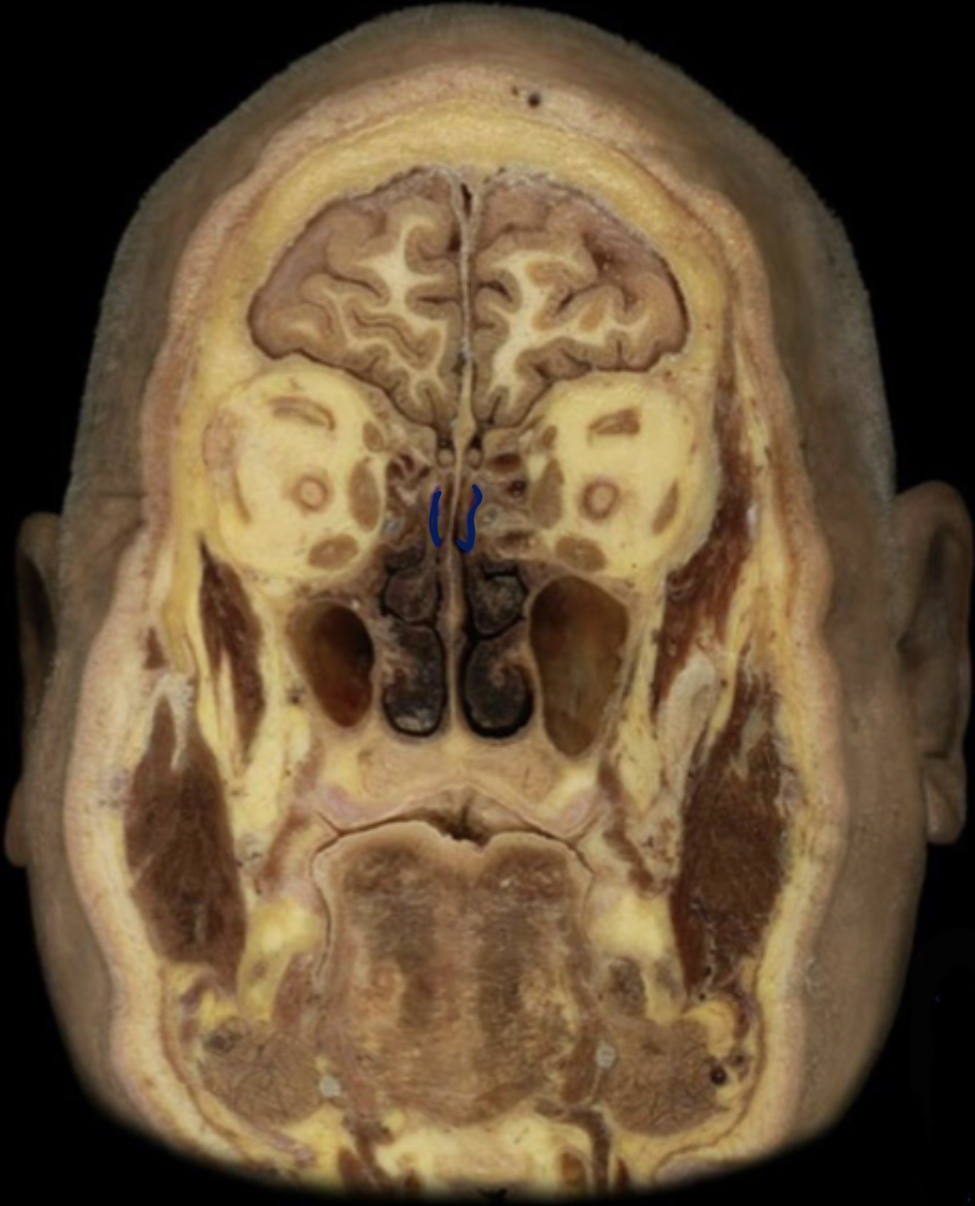

What structure is highlighted in blue?

Middle nasal concha